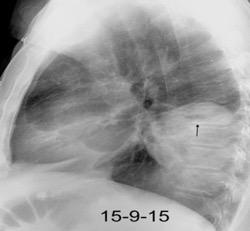

Tb con paquipleuritis calcificada, Hidroneumotórax. Cavidad apical conectada a pleura. Atelectasia redonda

Eyler WR et l. Rib enlargement in patients with chronic pleural disease . AJR 1996